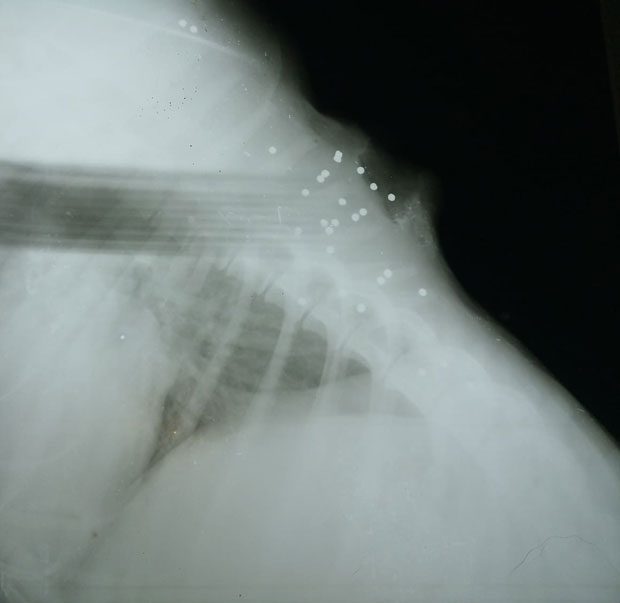

Χανιά 2019, περιοχή Μουρνιές. Τον πυροβόλησαν και στη συνέχεια τον τραυμάτισαν με αιχμηρό αντικείμενο..Είναι θλιβερό ότι πια δεν ξαφνιαζόμαστε. Ψάχνουμε φιλοξενία για την αποθεραπεία του! παρακαλούμε κοινοποιήστε.